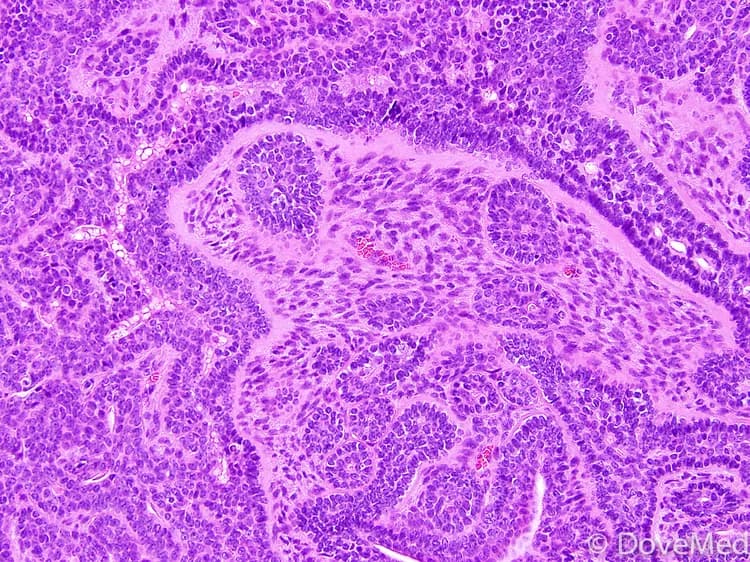

• A tissue biopsy of the tumor is performed and sent to a laboratory for a pathological examination. A pathologist examines the biopsy under a microscope. After putting together clinical findings, special studies on tissues (if needed) and with microscope findings, the pathologist arrives at a definitive diagnosis. Examination of the biopsy under a microscope by a pathologist is considered to be gold standard in arriving at a conclusive diagnosis

• Biopsy specimens are studied initially using Hematoxylin and Eosin staining. The pathologist then decides on additional studies depending on the clinical situation

• Sometimes, the pathologist may perform special studies, which may include immunohistochemical stains, molecular testing, and very rarely, electron microscopic studies to assist in the diagnosis

• Grossly, Basal Cell Adenomas of Salivary Glands are monomorphic, low-grade, encapsulated, and often cystic lesions

• A pathologist may use special studies such as special stains. Special stains (markers) used on biopsy samples may include keratin, alpha-1-antichymotrypsin, CEA, S100, vimentin, and actin